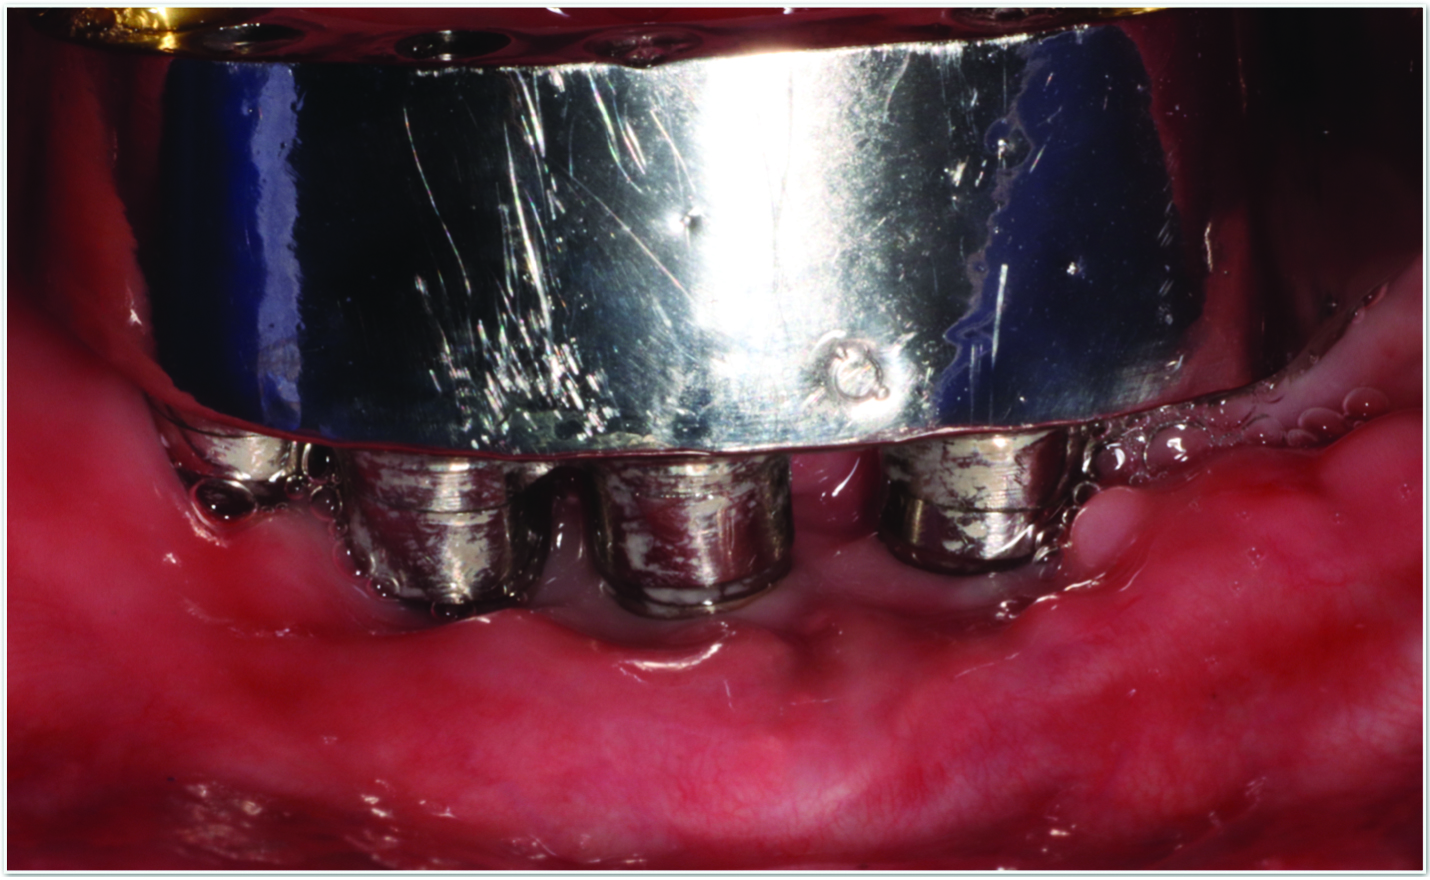

Fig 5 and Fig 6. Pre- (Fig 5) and post-treatment (Fig 6) photographs of a patient who received resective implant surgery to assess peri-implantitis at sites Nos. 14 and 15. Note the improved cleansability of the implants after surgery that opened the embrasure (Fig 6). The patient was placed on 3-month supportive peri-implant care post-surgery.

Figure 5

Figure 6

Surgical treatment encompasses both resective and regenerative approaches.41 During resective surgical therapy of peri-implantitis, the objectives are to remove excess granulation tissue, halt osseous cratering, and apically position the tissues, all of which may be done in combination with implantoplasty to smooth the threads of the roughened implant surface (Figure 5 and Figure 6).41 Conversely, regenerative surgical therapy involves the use of various combinations of bone grafts, membranes, and biologic materials to regenerate the lost implant-supporting structures.42